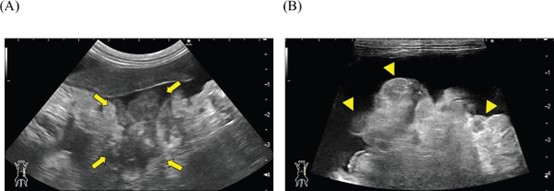

腹水分析显示总核细胞计数为1000个/μl,未发现肿瘤细胞或细菌感染,上清液比重为1.024,确认腹水为渗出液(下图)。

↑ 腹水沉渣细胞学检查。涂片显示细胞成分低,仅有少量轻度变性的中性粒细胞和巨噬细胞。未发现肿瘤细胞或细菌感染的证据。